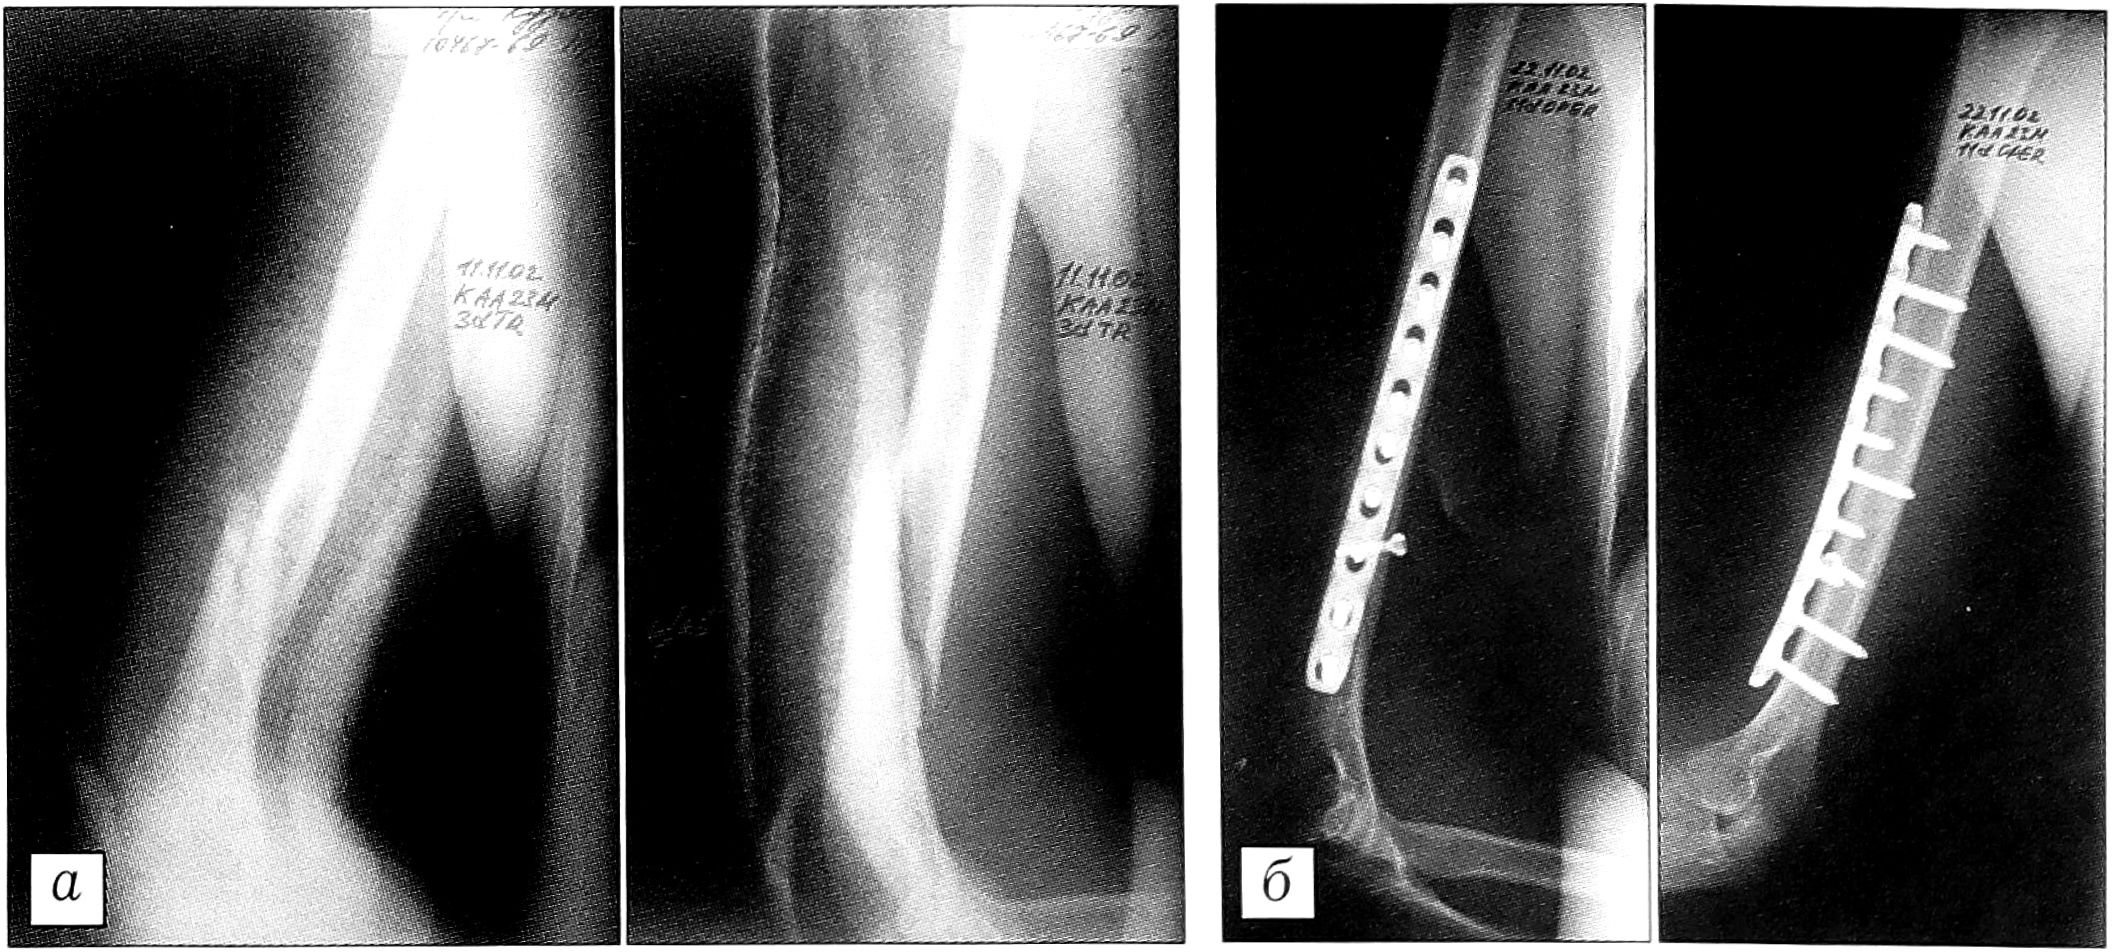

Пример. Больной К.,23 лет, госпитализирован в ЦИТО 11.11.02 с переломом нижней трети правой плечевой кости через 2 нед после получения травмы. 14.11.02 произведен подкожный остеосинтез правой плечевой кости пластиной LСР с сохранением надкостницы. Через 2 нед после операции пациент выписан на амбулаторное лечение с полным восстановлением обема движений (рис. 2).

Рис. 2. Больной К. Диагноз: винтообразный перелом нижней трети правой плечевой кости. а — рентгенограммы при поступлении; б — после остеосинтеза пластиной LCP.